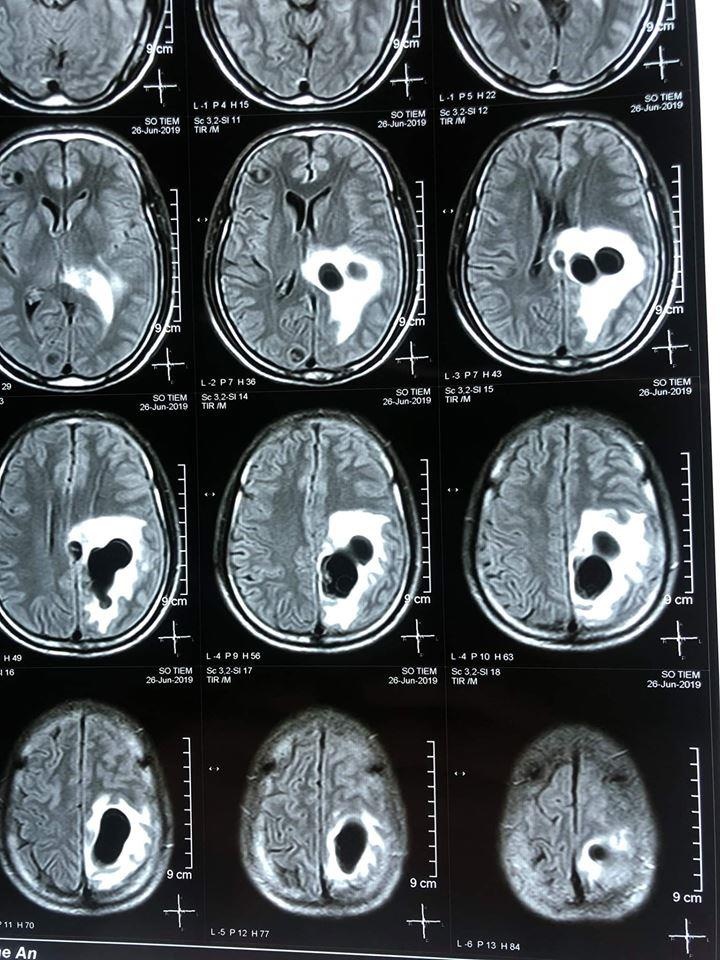

| Hình ảnh ổ sán trong não anh Sùng. Ảnh: BVCC. |

Qua kết quả chụp cắt lớp vi tính, các bác sĩ phát hiện có 5 ổ sán nằm rải rác trong não bệnh nhân. Trong đó, một ổ sán lớn gây phù não. Anh Sùng được chỉ định can thiệp ngoại khoa để lấy ổ nang sán khỏi não.